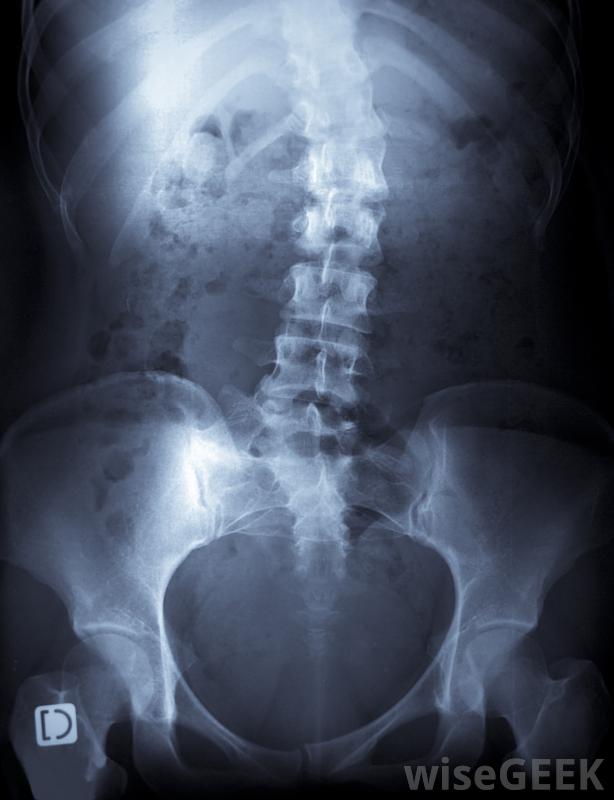

脊柱側凸是脊柱的一種側彎或側彎,它是一列被稱為"椎骨"的小骨柱,相互堆疊在一起;它從頸部后部開始,一直延伸到臀部頂部。雖然每個脊柱都有自然的前后曲線,但如果在青春期脊柱生長時形成了側彎,則可以使用脊柱側凸后支具來矯正曲線。如果沒有矯正,明顯的曲線可能會導致不平衡、肌肉無力、疼痛,甚至極端情況下會干擾呼吸。脊柱側凸會導致脊柱彎曲。脊柱側凸背帶是典型的治療曲線達到25度時使用的方法。一旦確定這是一個合適的治療過程,脊柱側凸背托通常會一直戴到脊椎停止生長。這通常意味著支架要戴好幾年。大多數支架都是在任何時候戴的,包括在睡覺的時候,雖然它們可以在洗澡時取下,但這一點很重要,因為這樣做的目的是使脊柱始終保持適當的對齊,這有助于脊椎的直線生長。然而,有些患者可能會被允許每天移除支架一到兩個小時來參加游泳等活動治療脊柱側凸時可佩戴背帶在過去,脊柱側凸背托的唯一類型是密爾沃基支具。雖然有效,但這種支具相當笨重,而且有固定頸部的金屬條,無法偽裝。現在,這是一種很普通的支撐方式,它是一種很普通的支撐方式,它是一種很普通的支撐方式,例如查爾斯頓或普羅維登斯,但沒有像波士頓矯正器那樣頻繁使用。脊柱側凸背托一般戴在t恤或汗衫上,最好是100%純棉,以防止皮膚刺激。鼓勵患者為了保持護具的清潔和保養,并密切監視皮膚,以防出現問題。盡可能戴緊護具可以防止摩擦。剛開始時可能會有點不舒服,因為它確實會限制活動,但是大多數脊柱側凸患者一旦適應了支架,就可以恢復所有的日常活動。